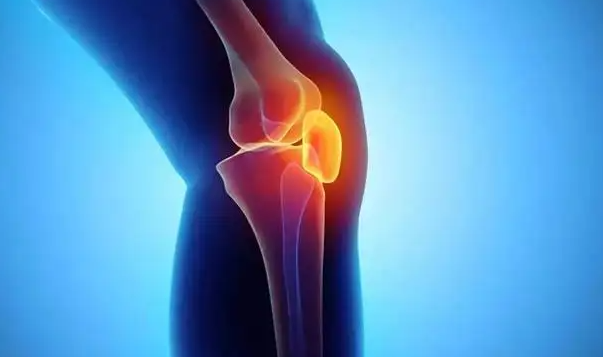

관절염이란 말 그대로 관절에 염증이 생긴것을 말합니다. 염증으로 인해 관절을 움직일때마다 통증이 생길 수 밖에 없습니다. 평소에 좋은 습관과 운동 그리고 식단 관리로 관절염 예방 해보시기 바랍니다.